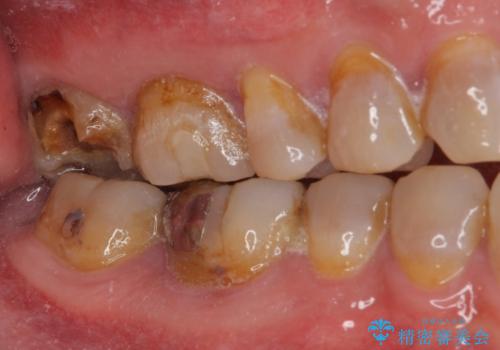

- 銀歯が外れてしまったとのことで来院された患者様です。

上顎奥の粘膜に近い部分で、外れた銀歯の下には大きく虫歯が広がっていました。

虫歯をしっかりと取り除き、ゴールドインレーにて修復することとしました。